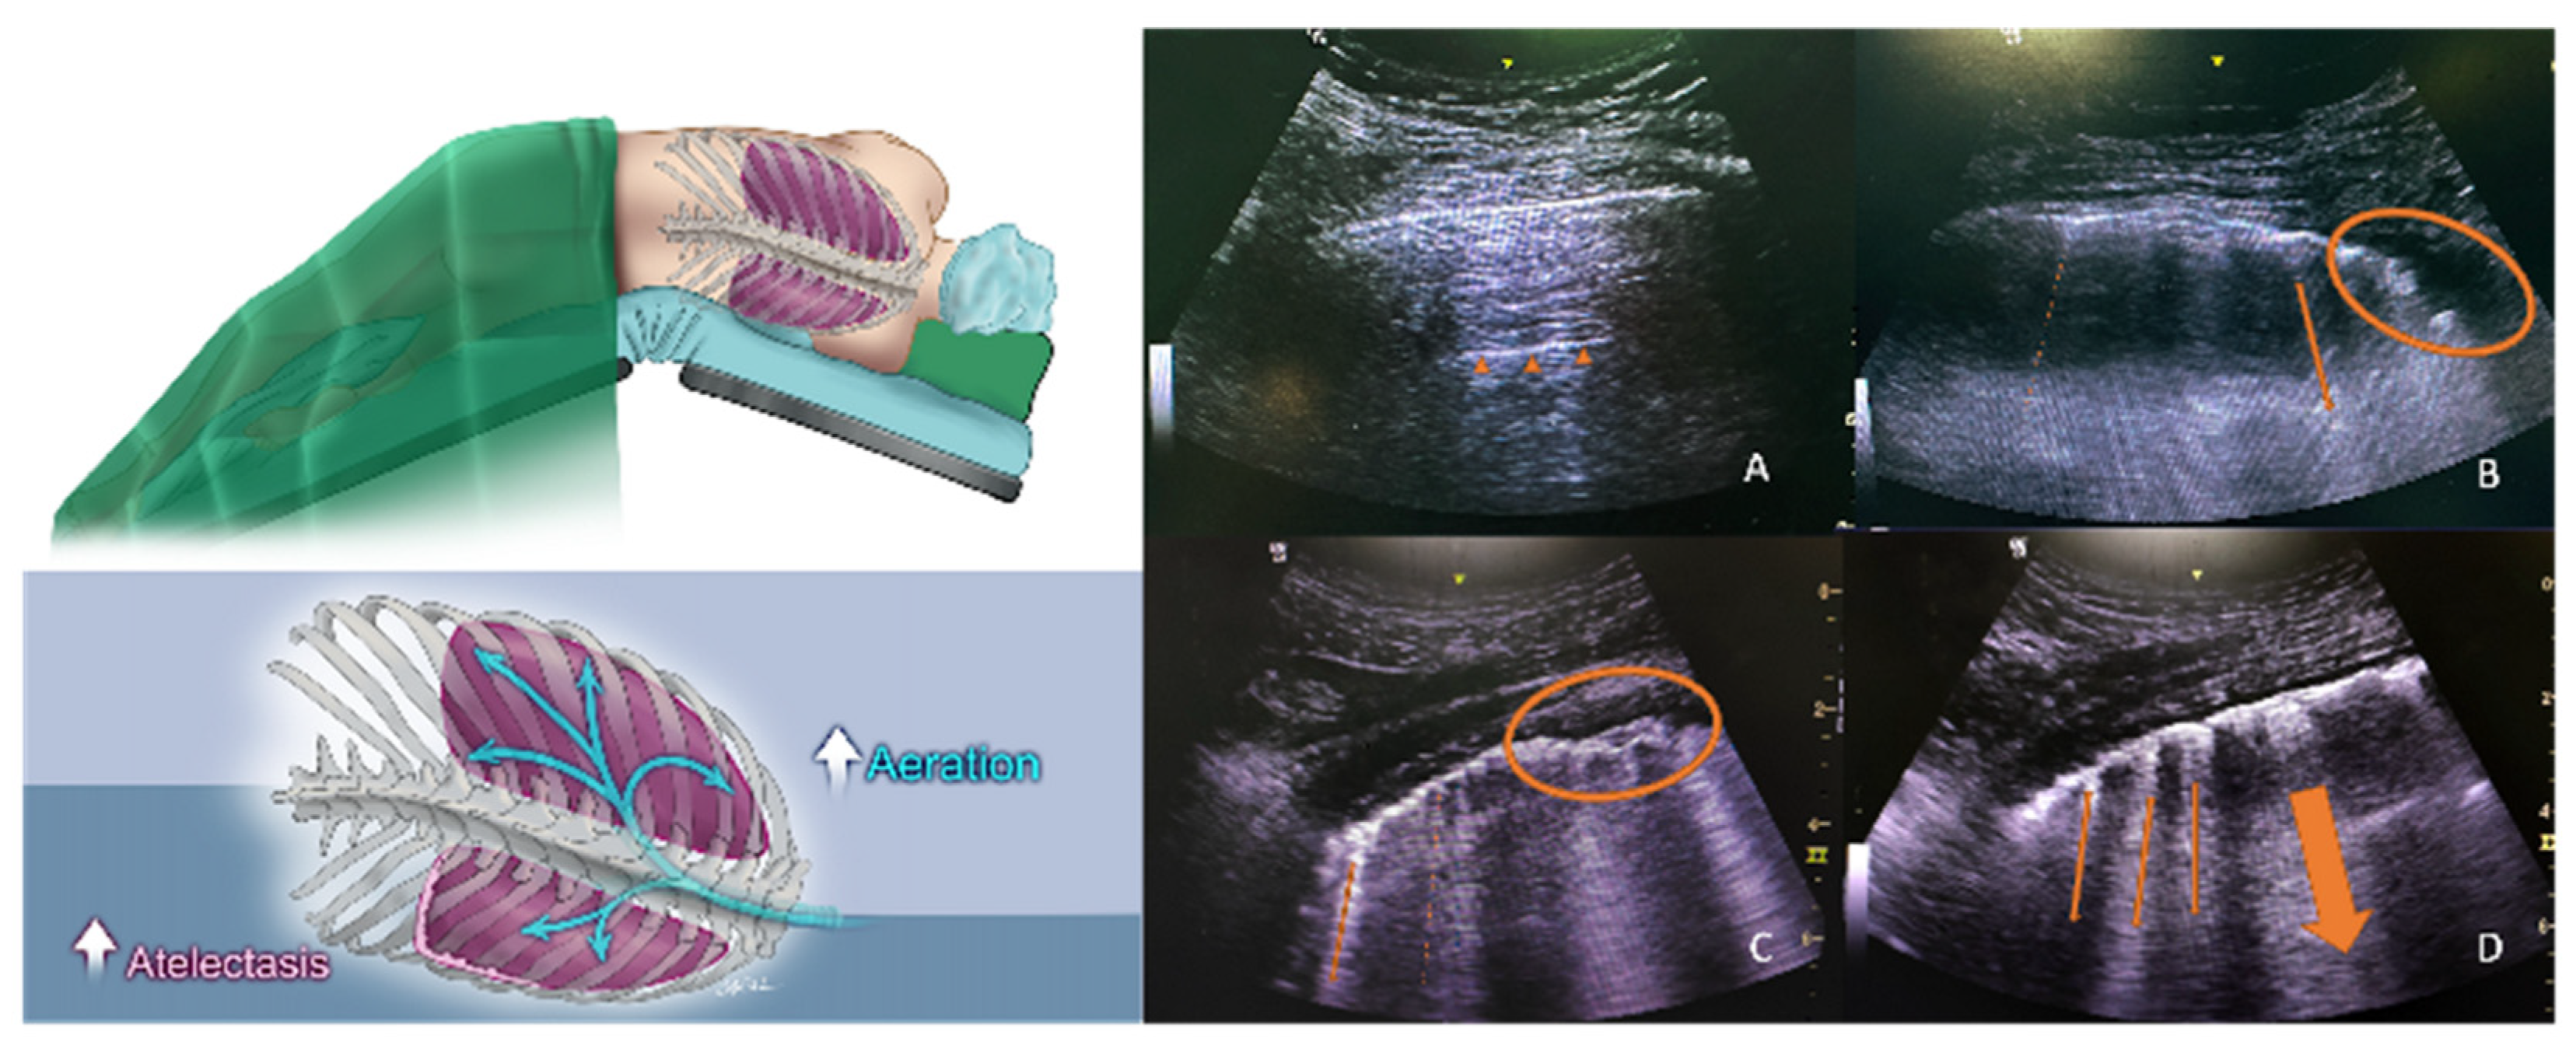

Monastesse et al. demonstrated a moderately correlated decrease in the PaO2/FiO2 ratio with a lower LUS in laparoscopic surgery patients who were operated on in the lithotomy position (r = −0.43) and, as expected, most LUS changes were observed in the inferior and posterior zones of the lungs [20]. Due to the surgical position, laparoscopic nephrectomy surgeries present a different perspective for respiratory investigations. Theoretically, with the lateral decubitus position, an increase in abdominal pressure and airway resistance is encountered, resulting in a decreased end-expiratory lung volume and static chest wall compliance in the “dependent” lung, which also receives the majority of the lung perfusion [21]. Therefore, consolidation and atelectasis are expected in the dependent lung during such surgeries, which may alter oxygenation, resulting in several pulmonary complications (Figure 5). Despite the abovementioned intraoperative changes in the dependent lung, the LUS of the dependent lungs cannot be considered as a major predictor of PPCs. Interestingly, only global (both lungs) LUS measurements showed significant changes when the groups were divided according to the presence of a PPC. The ultrasound scores for the upper and lower zones of the dependent lung did not show a statistically significant difference. Since our patients were operated on in the lateral position, one can assume that the condition of the “non-dependent” lung would be more clinically important.

Figure 5. Diagrams and example images of pre-extubation lung ultrasound. (A) shows the non-dependent lung zone 4 with 0 points; small triangles indicate the physiologic A-line. (BD) show the dependent lung zone 4 in different patients. The thin and dashed arrows indicate the B-lines. The thick arrows indicate converged B-lines, and circles indicate consolidation areas (3 points).